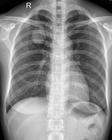

X線胸片可見圓、橢圓形,大小不等實性或囊性陰影,囊內密度不均,常可發現牙齒或鈣化影,胸部CT掃描可更清楚顯示囊內結構有助確診。必要時可行經胸壁肺活檢或開胸探查確診。